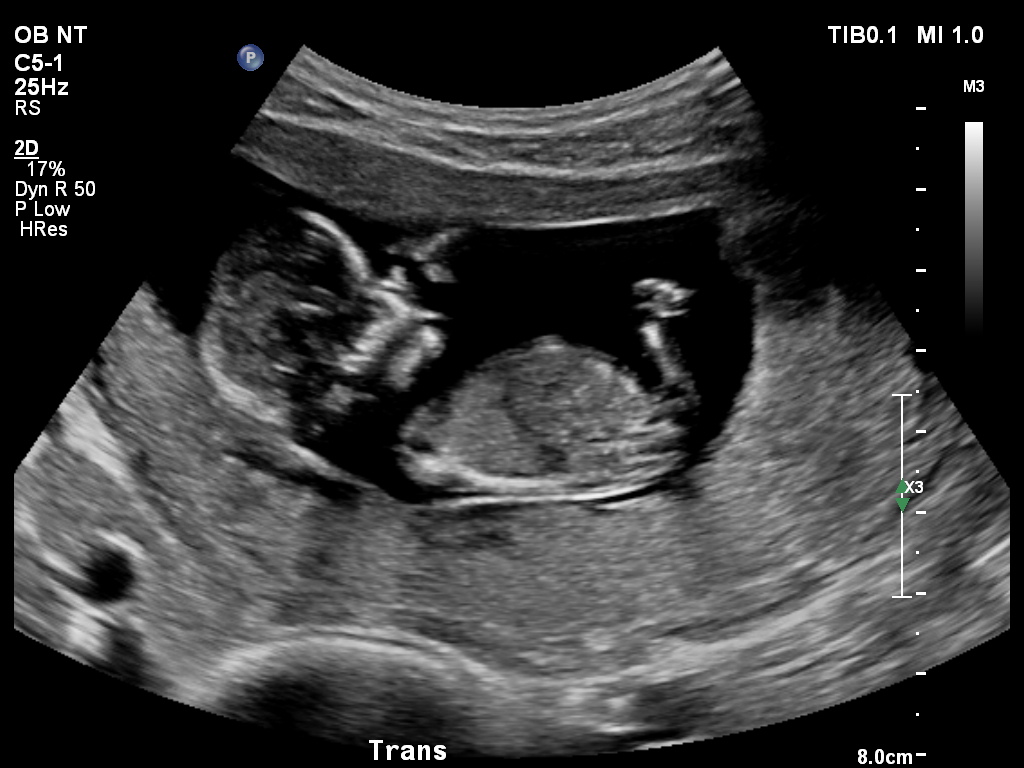

What Does Nt Mean On An Ultrasound / NT Screening: What is it? What does it mean if you're high ... - This means that you get to watch your child move within the womb.. What do ultrasound abbreviations and initials mean? The nuchal translucency scan (also called the nt scan) uses ultrasound to assess your developing baby's risk of having down syndrome (ds) and some other chromosomal abnormalities, as well as major congenital heart problems. An nt scan will measure this using ultrasound technology when your baby is between 11 and 14 weeks old or measures between 45mm and 84mm. The nuchal translucency or nt scan is an ultrasound test to measure the thickness of this fluid accumulated in the space behind the fetus's neck tissue. First trimester screening, also called the first trimester combined test, has two steps:

An nt scan is a common screening test that occurs during the first trimester of pregnancy. Nuchal translucency (nt) ultrasound is a diagnostic prenatal screening assessment prescribed to detect chromosomal abnormalities associated with down syndrome (trisomy 21), one of the most common genetic conditions affecting 1 in 700 u.s. However, even a normal nt measurement would need to be considered with the blood test result and other factors, such as your age. The nuchal translucency or nt scan is an ultrasound test to measure the thickness of this fluid accumulated in the space behind the fetus's neck tissue. Nt focuses on a small, clear space at the back of a growing baby's neck called the nuchal fold.

One color will represent flow in the veins while the other color will represent flow in the arteries depending on the direction of flow in relation to the probe. Ultrasound is a type of imaging which is used to view the heart, blood vessels, kidneys, liver and other organs. In addition, a measurement of the fluid underneath the skin along the back of the baby's neck, called the nuchal translucency (nt), will be taken. The nt is considered large when it is 3.0 mm (about 1/8 inch) or more. This test measures the size of the clear tissue, called the nuchal translucency, at the back of your. Nuchal translucency (nt) normal range pregnancy is a time when people tend to learn a lot of new terminology. Most babies with a large nt will be healthy at birth. Nuchal translucency is a screening test to determine risk of chromosome abnormalities in a fetus. This is another test that checks for birth defects. This is the ultrasound typically completed at the 12 week mark of pregnancy. Nuchal translucency is usually done between the 11th and 14th week of pregnancy. Since chromosomal abnormalities can result in impaired cardiovascular development, a nuchal translucency scan is used as a screening, rather than. An nt scan is a common screening test that occurs during the first trimester of pregnancy.

Nuchal translucency (nt) measurement nuchal translucensy (nt) is the clear space in the tissue of your developing baby's neck. The fourth dimension is time, because it is a video and not just a still image. An nt scan will measure this using ultrasound technology when your baby is between 11 and 14 weeks old or measures between 45mm and 84mm. In addition, a measurement of the fluid underneath the skin along the back of the baby's neck, called the nuchal translucency (nt), will be taken. Much like the 3d ultrasound, a 4d ultrasound is typically used as a keepsake. Ultrasounds guide future mums during the whole pregnancy process and are essential to understand how the baby progresses, thanks to the ultrasound pregnancy is confirmed, and is possible to know the number of babies they are expecting, ruling out possible fetal abnormalities and reveal the. Ultrasound devices range with frequencies from 20khz to several gigahertz. The ultrasound marker is nuchal translucency (nt) thickness.

During the ultrasound examination, a thin layer of fl uid at the back of the neck called the nuchal translucency (nt) is measured. What do ultrasound abbreviations and initials mean? Much like the 3d ultrasound, a 4d ultrasound is typically used as a keepsake. The nuchal translucency scan (also called the nt scan) uses ultrasound to assess your developing baby's risk of having down syndrome (ds) and some other chromosomal abnormalities, as well as major congenital heart problems. Nuchal translucency is the collection of fluid which is under the skin at the back of your baby's neck. The ultrasound marker is nuchal translucency (nt) thickness. Nt focuses on a small, clear space at the back of a growing baby's neck called the nuchal fold. At times, the nuchal translucency test may add on ultrasound markers, such as measuring a baby's.

The ultrasound nt scan or nuchal translucency scan is an ultrasound to measure the amount of fluid that has been collected in the back of the neck of the fetus. Since chromosomal abnormalities can result in impaired cardiovascular development, a nuchal translucency scan is used as a screening, rather than. Nuchal translucency is usually done between the 11th and 14th week of pregnancy. Nt focuses on a small, clear space at the back of a growing baby's neck called the nuchal fold. Nuchal translucency (nt) measurement nuchal translucensy (nt) is the clear space in the tissue of your developing baby's neck. A nuchal scan or nuchal translucency (nt) scan/procedure is a sonographic prenatal screening scan to detect chromosomal abnormalities in a fetus, though altered extracellular matrix composition and limited lymphatic drainage can also be detected. Ultrasound measurement and a blood test. The ultrasound doctor will enter the nt measurement, blood test results and other factors into a database to generate a more accurate estimation of the chance of down's syndrome. When the nasal bone is absent at 11 to 12 weeks, while the other ultrasound markers and serum biochemistry are normal; Among the many terms you will learn and become familiar with is a nuchal scan. Substances in your blood which are markers of down syndrome and a specific ultrasound marker will be measured. However, even a normal nt measurement would need to be considered with the blood test result and other factors, such as your age. It should not be confused with the nuchal fold, which is seen in the second trimester.